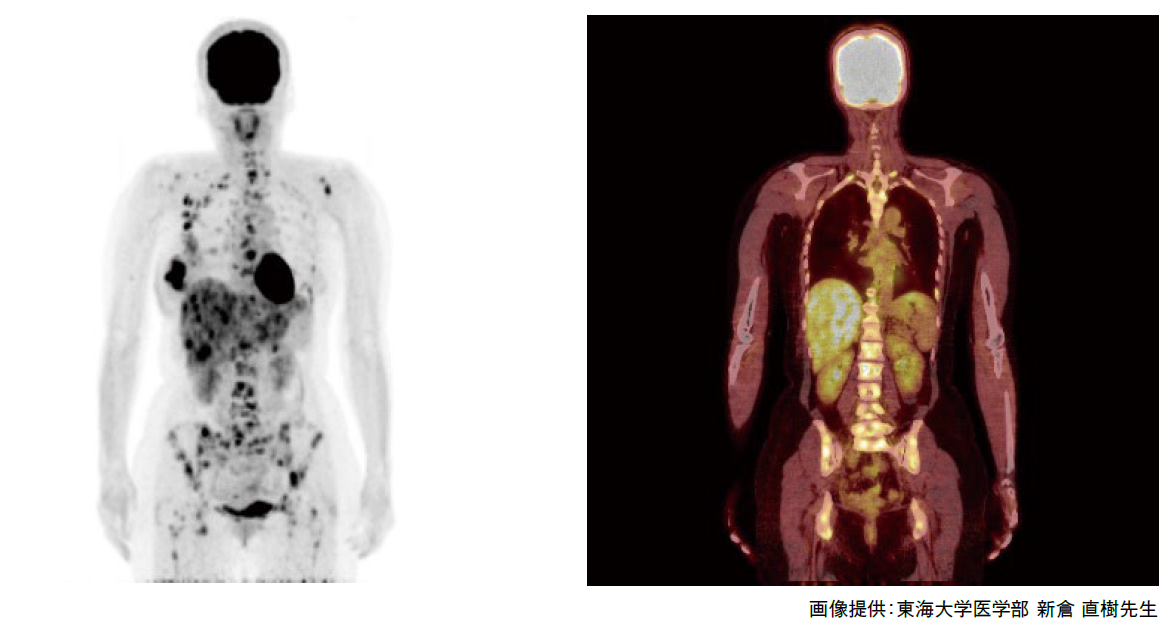

前立腺がんの検査 画像検査 Ct Mri 骨シンチグラフィ で何がわかる

検査の流れ 50歳を過ぎたら注意 前立腺がん 患者 ご家族の皆様

確定診断までの流れ がんの治療法 詳しく知りたい 前立腺がん

確定診断までの流れ がんの治療法 詳しく知りたい 前立腺がん